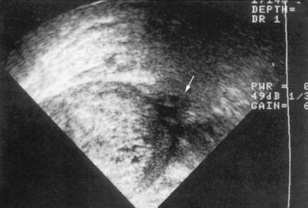

Ultrasonography is a non-invasive technique that involves high-frequency sound waves. It can accurately assess the size, shape and position of the kidney, and can also distinguish solid masses and renal cysts (Figs 8.17 and 8.18). Dilatation of the pelvicalyceal system and upper ureters can also be detected – suggesting the presence of urinary tract obstruction. This is a major cause of reversible renal failure, and can be treated if detected early enough. Transrectal ultrasound (TRUS) can also assess prostate size and be used to guide a prostate biopsy (Fig. 8.19). Renal vein thrombosis can be detected with Doppler ultrasonography, and arterial Doppler studies can be used to identify renal artery stenosis. The specificity and sensitivity of ultrasound investigations are very operator-dependent.

image

Fig. 8.17 Ultrasound scan showing the typical appearance of polycystic kidneys. There are multiple cysts (arrows) in the parenchyma.

(From Lloyd-Davis RW et al, 1994. Color atlas of urology, 2nd edn. Mosby Year Book.)